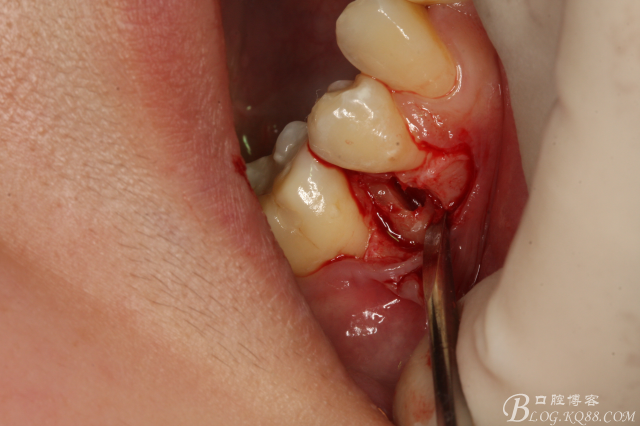

圖5.局部麻醉下、在44近中做垂直小切口,切口不要超過膜齦聯(lián)合。

圖6.齦溝內(nèi)水平切口

圖7.翻小瓣。暴露45牙根斷面